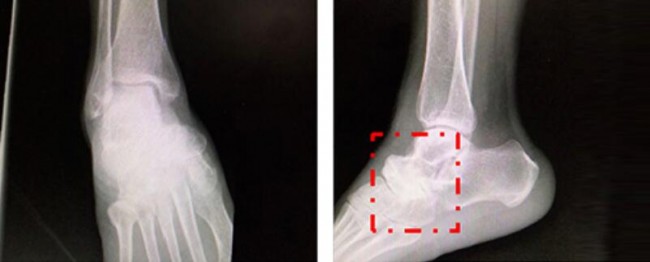

经怀集县人民医院进行X线片、CT、MR等传统影像检查,初步诊断为:1.右足舟骨坏死。2.右距舟关节骨关节炎。3.右跟骰关节骨关节炎。拟行右距舟关节、跟骰关节融合术。

丁焕文教授团队结合患者症状、体征临床诊断为Muller-Weiss病。通过3D精准定位确认患者病变部位为附横关节。通过会诊讨论,决定为患者实行“足内侧柱延长、距舟关节融合、距骨骰骨融合固定”手术。